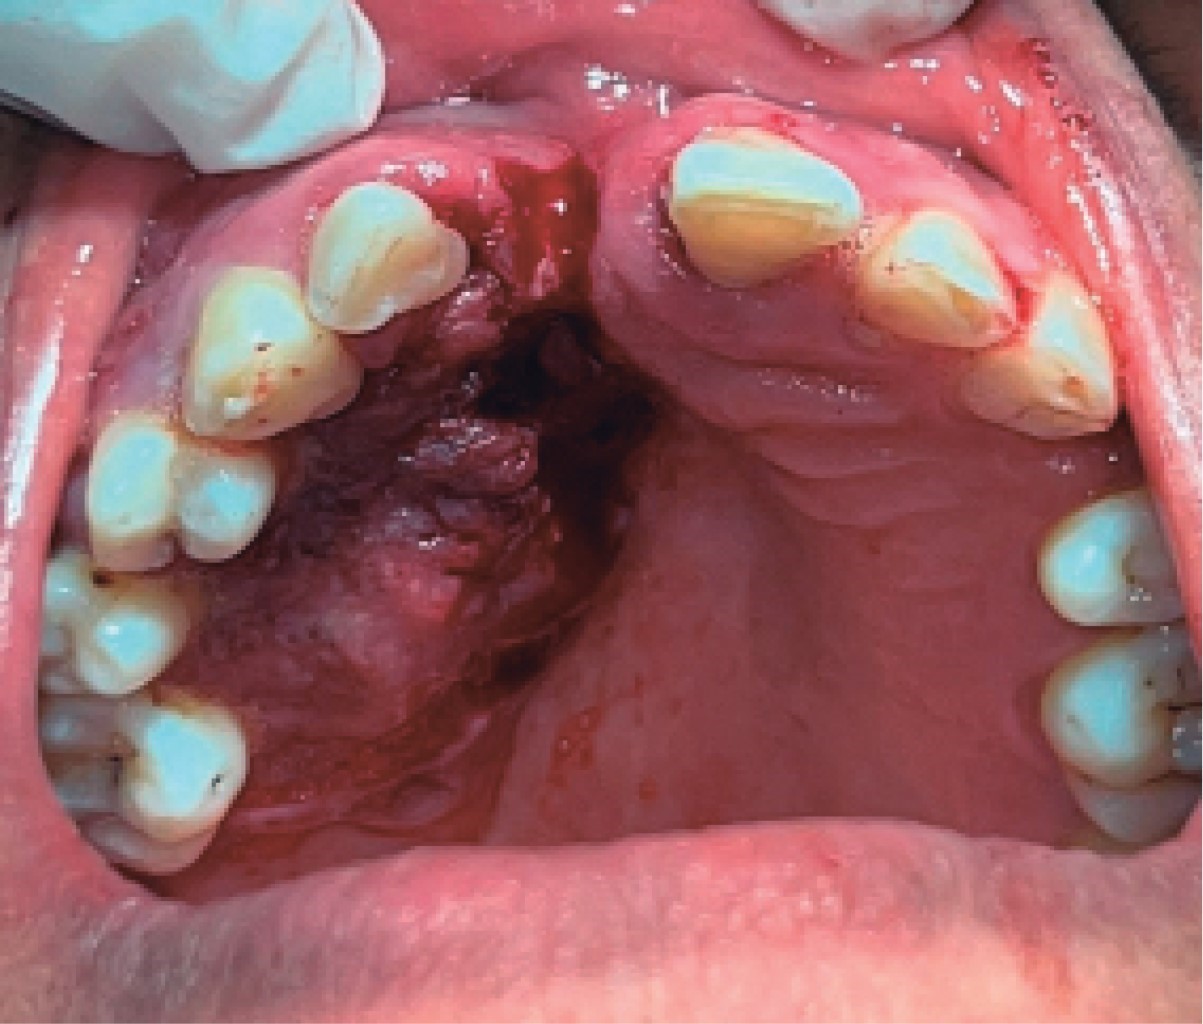

Oral squamous cell carcinoma of the palate: a case report.

Oral cancer represents a serious health problem worldwide due to its significant morbidity and mortality, it is the sixth leading cause of cancer death and has a global 5-year survival rate of 50%, largely due to the lack of recognition in early stages by patients and health professionals themselves, which causes a serious delay in diagnosis and treatment. We present the case of a 64-year-old woman with long-standing ulcers in the oral cavity who went to multiple health professionals without being diagnosed in the initial stages of the disease. She went to the Autonomous University of Tlaxcala where oral squamous cell carcinoma (OSCC) in the maxilla was diagnosed. This article emphasizes the recognition of clinical signs and precipitating factors that may generate suspicion of malignant growth and thus raise awareness among health professionals to promote prevention.

Figure 2